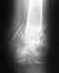

Недавно был у травматолога. Мне сделали рентген колена в двух проекциях, и по этому рентгену врач сказал, что с ним всё впорядке, т.к. болевых ощущений уже не наблюдалось. Но после каждой тренировки всё равно боль возобновляется.Очень не хотелось бы бросать тренировки, посоветуйте пожалуйста что-нибудь.Очень расчитываю на ваши компетентные комментарии. Заранее спасибо.